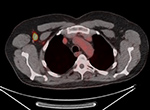

Thyroid imaging with pinhole collimator after the injection of free Tc-99m pertechnetate shows a rounded focal photopenic defect in the region of the left lower thyroid lobe caused by a nonfunctional photomultiplier tube. Focal intense activity seen in the right antecubital region and along the right lateral abdominal wall on Tc-99m MDP scan is related to extravasation of radiopharmaceutical at the injection site with scatter of photons from the forearm to the abdominal wall (narrow angle scatter). Fused axial FDG PET-CT (B), PET axial (C), CT axial (D) and MIP PET (E) images demonstrate intensely FDG avid lymph node in the right axilla. Infiltration of FDG at the injection site in right antecubital fossa results in lymphoscintigraphy with FDG migrating to the regional nodal basin via the lymphatic ducts.

Fused axial FDG PET-CT (B), PET axial (C), CT axial (D) and MIP PET (E) images, demonstrate intensely FDG avid lymph node in the right axilla. Infiltration of FDG at the injection site in right antecubital fossa results in lymphoscintigraphy with FDG migrating to the regional nodal basin via the lymphatic ducts. Technetium 99m MDP whole body bone scan shows photopenic defect on the midline pelvis from the attenuation of a belt buckle.